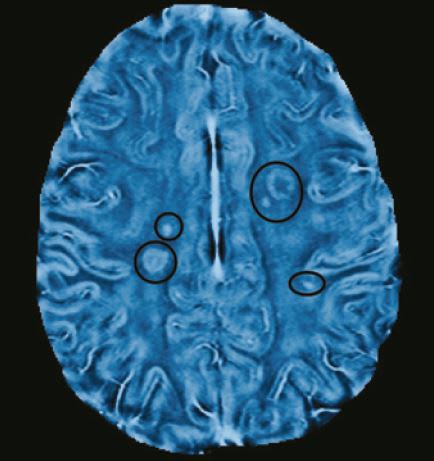

New MRI Technique for MS Research

Scientists at the University of British Columbia, Vancouver, Canada, have developed a new MRI technique that, they say, detects signs of multiple sclerosis (MS) in finer detail than ever before, which provides a more powerful tool for evaluating new treatments.

The technique analyzes the frequency of electromagnetic waves collected by an MRI scanner, instead of their size. Although analyzing the number of waves per second had long been considered a more sensitive way of detecting changes in tissue structure, the math needed to create usable images had proved daunting.

The researchers applied their method to 20 MS patients, who were scanned once a month for six months using both conventional MRI and the new frequency-based method.

Once lesions in the myelin appeared in conventional MRI scans, the scientists looked at earlier frequency-based images of those patients. And, by examining the precise areas of those lesions, they found frequency changes, which indicate tissue damage, at least two months before damage appeared on conventional scans.